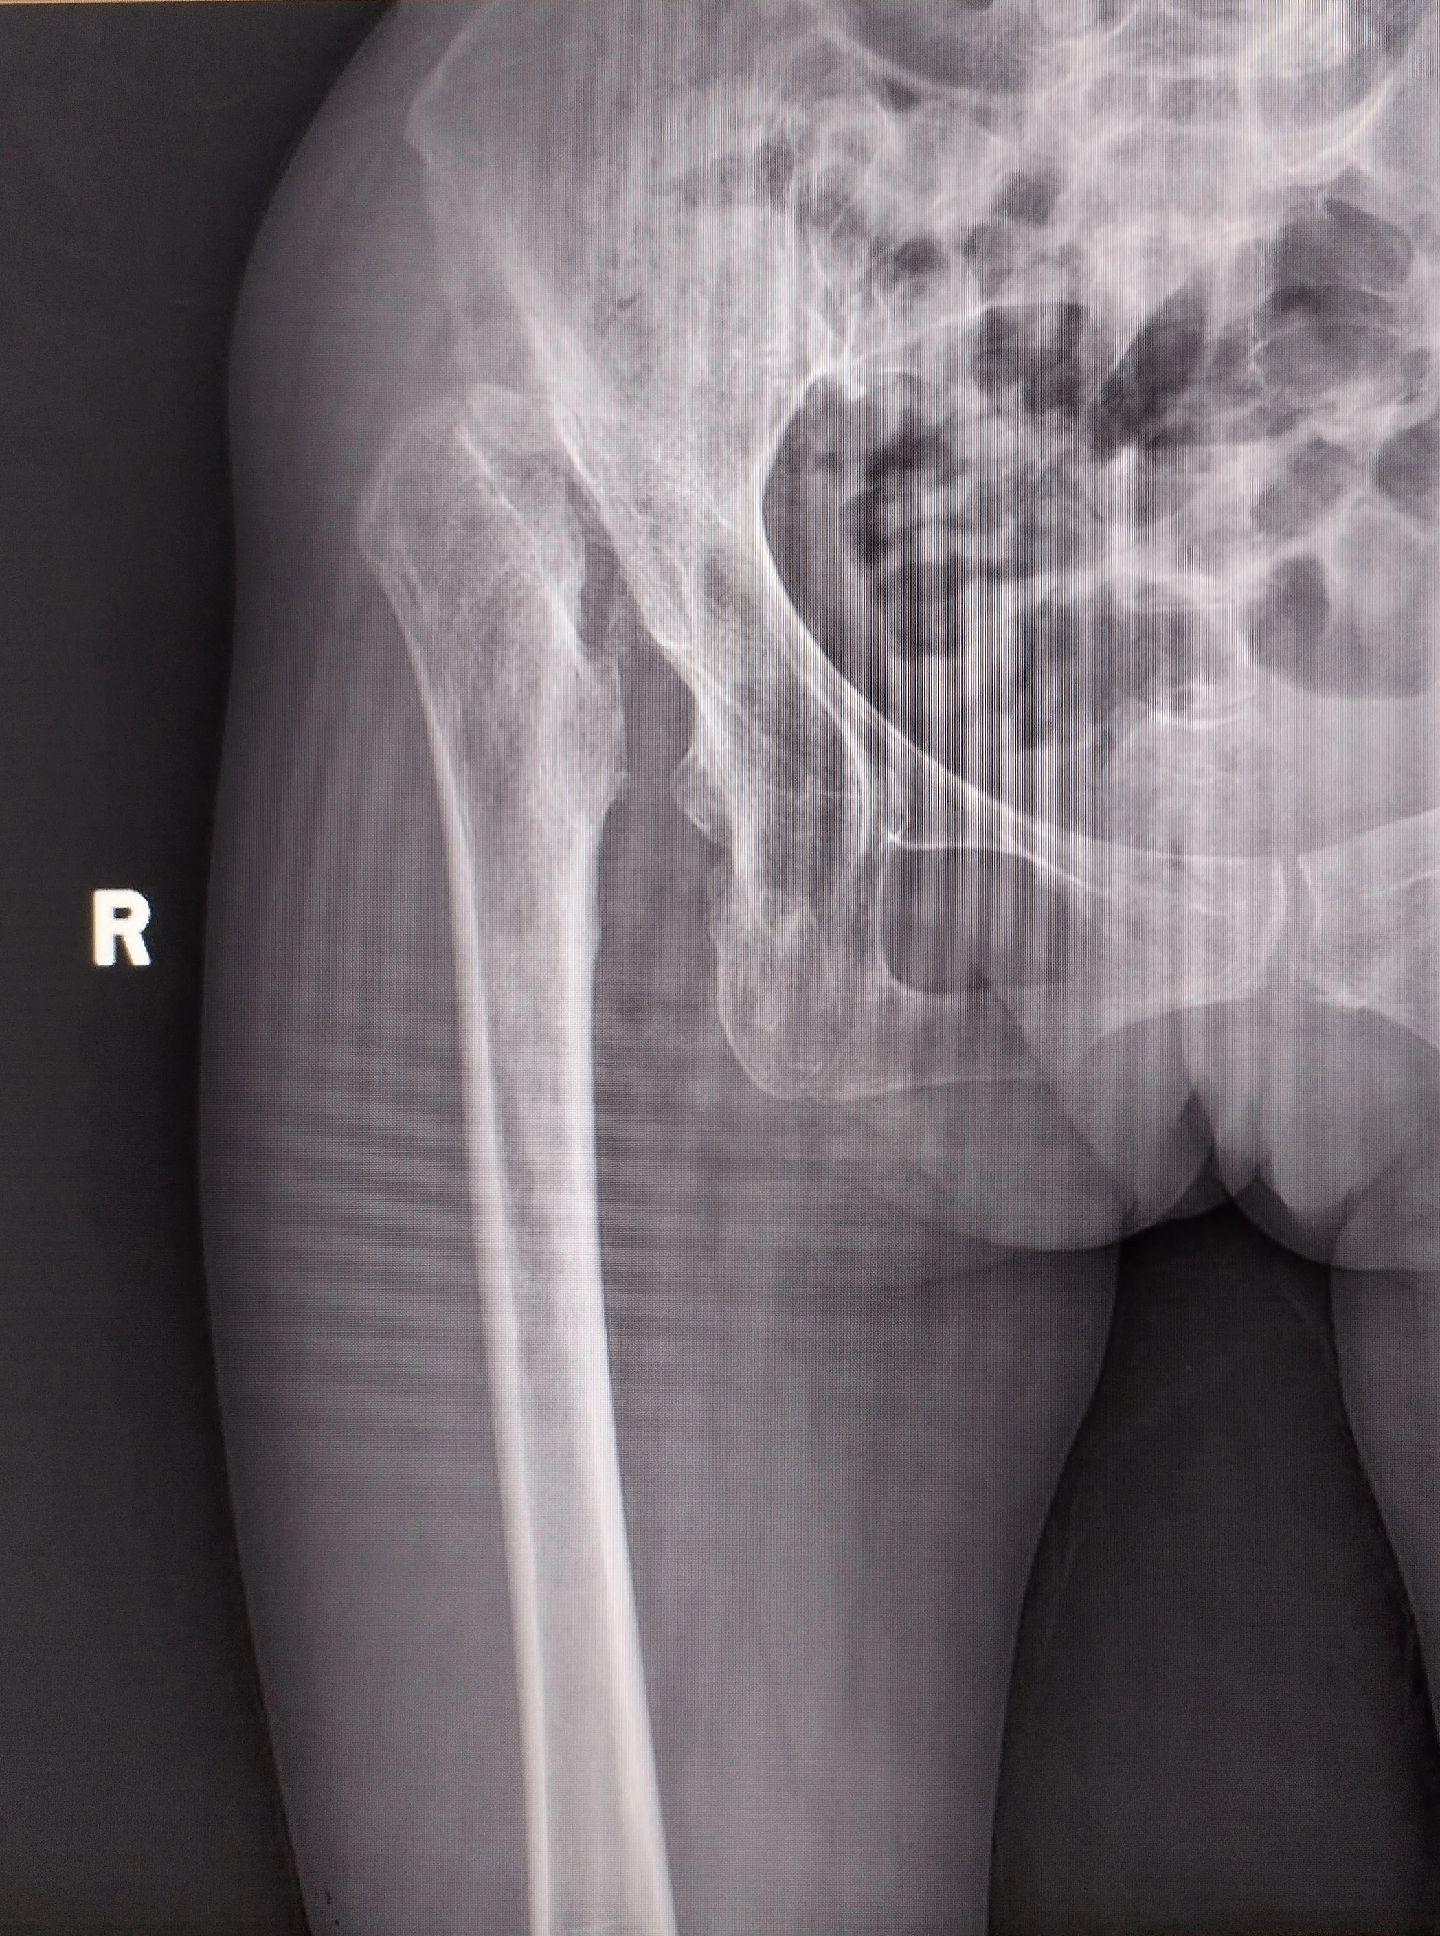

髋关节置换。DDH(先天性髋关节发育不良)四型高脱,要乐观,相信目前的技术,要有信心🌹